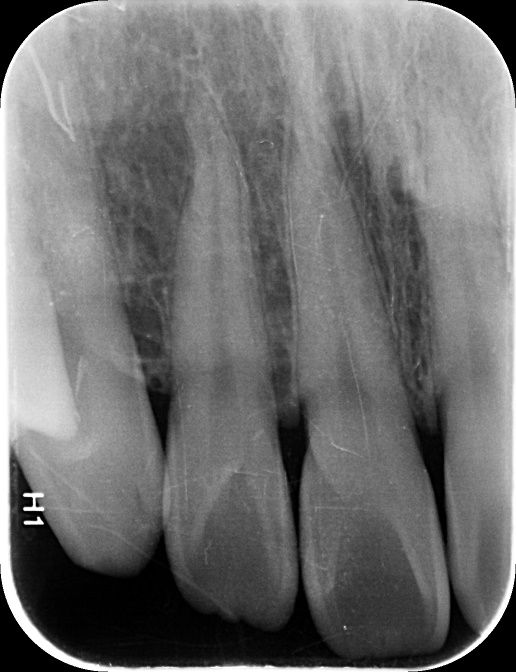

앞니 사이 인접면 충치가 있나요?(사진 첨부)

12, 11, 21, 22 번 4개 앞니 치아들에 대해서

• 1번 째 사진

엑스레이 상으로는 11과 12번의 사이, 21과 22의 사이에 충치가 있는 것으로 보이는데 맞나요?

실제로 바람불어서 긁어봐야 판단이 설 것 같긴한데 일단 엑스레이만 봐서는 관리를 잘한다고 해서 진행을 멈출 사이즈의 충치는 아닌 것 같은데, 지금처럼 인접면 충치의 경우에는 충치부위에 기구접근이 안되기 때문에 딱 충치부분만 제거를 할 수가 없어요. 그래서 좀 더 커질때까지 두고 보자vs지금 치료를 하자 이렇게 나뉜 것 같은데 원래 정석적으로는 바로 치료를 하는게 맞긴 합니다만, 치료를 해서 얻는 것보다 정상치질을 더 제거해야해서 잃는 실이 더 많다고 판단이 되면 좀 더 있다가 하기도 합니다. 이런 애매한 경우는 환자분께서 결정을 하시면 될 것 같습니다.

1. 법랑질 수준에 국한된 충치입니다.

2. 심미적으로 해당 부위가 검게 보이지 않는다면 관리를 하면서 지켜볼 수도 있습니다. 다만 겉으로 보기에는 검게 보인다면 치료를 하는 것이 맞으며 이는 심미적인 이유 때문입니다.

3. 11, 21 모두 치아에 일부 충치가 보입니다. 따라서 2곳 모두 치료해야할 것으로 보입니다.

엑스레이 상으로는 충치가 크게 보이진 않습니다. 저정도라면 저도 일단은 관리를 잘하시면서 지켜보라고 할것같습니다.

사진으로 보기에는 초기 우식이 보이기는 합니다. 하지만 ㅣㅊ료여부는 육안으로 확인을 해야알수가 있어요.

사진응 앞뒤가 겹쳐진 2차원 모잉야지만 충치는 3차원 공간으로 분석을 해야 하기 때문이에요.